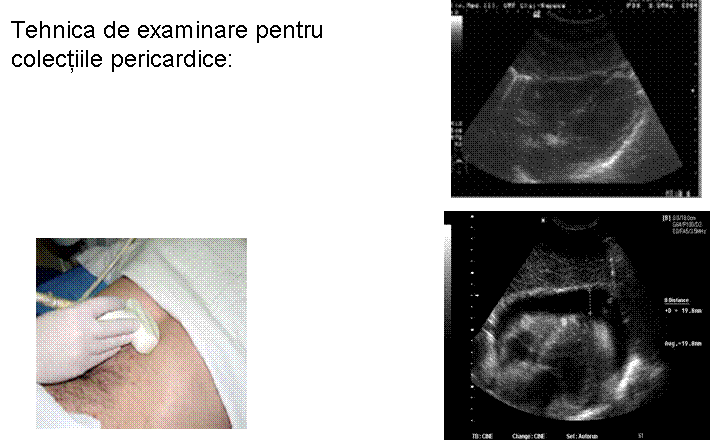

TRAUMATISM ABDOMINAL EXAMINARE FAST